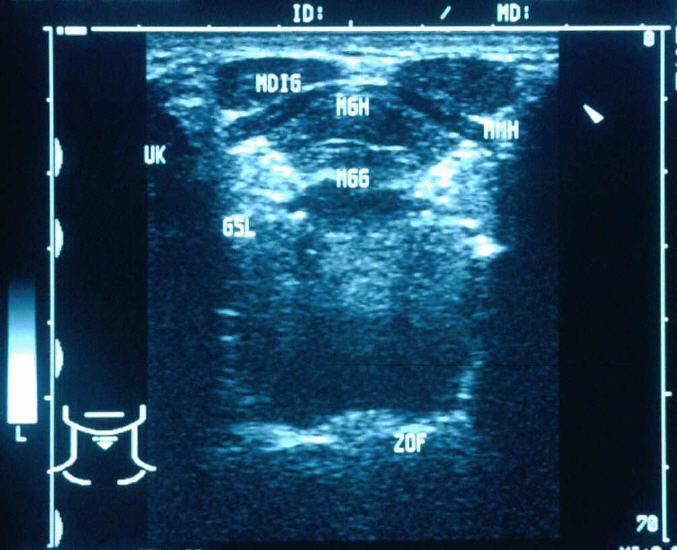

Mit Hilfe der Ultraschalldiagnostik können plötzlich aufgetretene Veränderungen im Kopf- Hals- Bereich wie Lymphknoten- vergrößerungen, Halszysten, Veränderungen an der Ohrspeicheldrüse oder auch Speichelsteine im Bereich der Unterkieferspeicheldrüse sicher erkannt und diagnostiziert werden. Der Ultraschall wird auch bei entzündlichen Erkrankungen der Nasennebenhöhlen (z. B. Sinusitis) eingesetzt. Der Ultraschall ist ein für den Patienten schmerzloses und nicht belastendes Verfahren und kann deshalb auch idealer Weise zur Verlaufsbeobachtung herangezogen werden.

Ebenfalls unentbehrlich ist der Ultraschall in der Vorsorge und in der regelmäßigen Nachsorge bei Tumorerkrankungen im Kopf-Hals-Bereich.

Im Bereich der Ultraschalldiagnostik ist ebenfalls die sonographisch kontrollierte Entnahme von Gewebeproben hervorzuheben. Unter „sonographischer Sicht“ wird mit Hilfe einer dünnen Nadel ein kleiner Gewebezylinder entnommen und zur Begutachtung eingeschickt.

Die Ultraschalldiagnostik wird durch die Farbdoppler- Sonographie ergänzt.